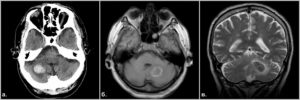

Обширный инсульт мозжечка

Обширный инсульт с поражением правого или левого полушария считается чрезвычайно серьезной патологией с высоким риском летального исхода.

Он наблюдается в зоне кровоснабжения верхней мозжечковой артерии или задней нижней при закрытии просвета позвоночной артерии.

Поскольку мозжечок снабжен хорошей сетью коллатералей, и все три основные его артерии связаны между собой, то изолированно мозжечковая симптоматика практически никогда не возникает, и к ней добавляются стволовые и общемозговые симптомы.

Обширный инсульт мозжечка сопровождается острым началом с общемозговой симптоматикой (головная боль, тошнота, рвота), расстройствами координации и моторики, речи, равновесия, в ряде случаев возникают нарушения дыхания и сердечной деятельности, глотания вследствие поражения ствола мозга.

При повреждении трети и более объема полушарий мозжечка течение инсульта может стать злокачественным, что обусловлено сильным отеком зоны некроза.

Увеличенный объем ткани в задней черепной ямке приводит к сдавливанию путей циркуляции ликвора, наступает острая гидроцефалия, а затем – сдавление ствола мозга и гибель больного.

Диагностика мозжечкового поражения

Составить полную клиническую картину заболевания можно только в стационаре. Доктор собирает анамнез, назначает МРТ или КТ головного мозга для выявления очагов поражения. Пациент сдает анализы и проходит ЭКГ. Диагностика позволяет установить тип инсульта и подобрать оптимальные методы лечения.